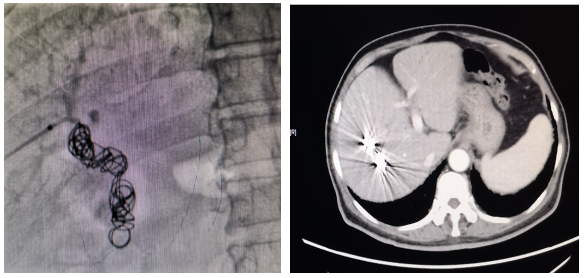

患者肿瘤紧邻右肝蒂,需要行右半肝切除,但sFLR<30%,残肝体积不足,选择PVE进行转化,在等待肝脏体积增长的同时,每天口服仑伐替尼 8mg。PVE 8周后患者sFLR达到35%,复查AFP 164 ng/ml。对该患者行腹腔镜下右半肝切除,目前无瘤生存16个月。

图示:PVE照片及PVE后8周肝脏增强CT

患者肝脏储备功能不足,残肝体积过小,选择PVE进行转化。PVE等待肝脏增生期间,选择TKI仑伐替尼治疗控制肿瘤,最终转化成功,完成了右半肝切除,患者顺利出院。此例患者高龄,采用“PVE+TKI”的策略获得了手术机会,在手术安全性和肿瘤学上均取得满意